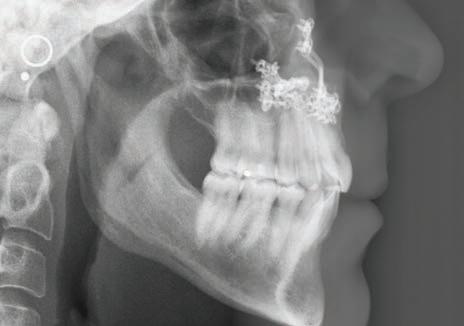

The post-treatment panoramic radiograph (Figure 8) highlights the maxillary surgical fixation hardware used to stabilize the three segments. Root angulation of tooth #19 appears imperfect but is similar to its pretreatment position and not reflected in the left posterior occlusion. Overall periodontal support and root length is largely unchanged following comprehensive orthodontic and surgical treatment.

The post-treatment cephalogram, its tracing and the cephalometric values (Figure 9a and 9b) demonstrate a slight increase in the SNA value and a corresponding increase in the ANB value with anterior movement of A-point. There were no other significant changes in the cephalometric measurements, including mandibular incisor position. It remained the same after the resolution of crowding and controlled space closure.

Figure 8: Post-treatment panoramic radiograph

Figures 9a and 9b: Post-Treatment cephalometric radiograph and analysis